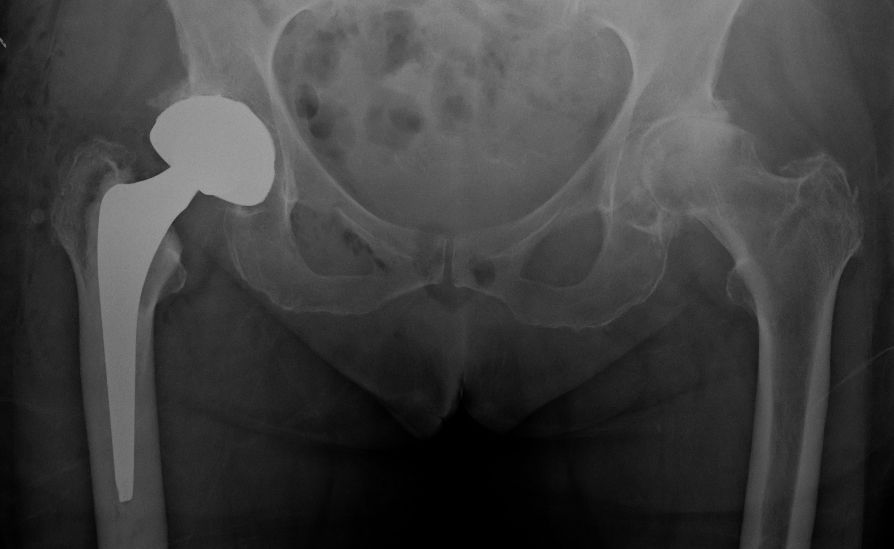

Dual mobility LDH THA

The DM design consists of a small femoral head (22 or 28mm), captive and mobile within a polyethylene (PE) liner (Fig. 3).

In turn, the large PE liner ball articulates with a highly polished metallic acetabular shell. The PE large head diameter is usually 6–8mm smaller than the outer metallic shell. There are two distinct articulations: a small articulation between the head and the PE liner and a large articulation between the PE head and the acetabular shell. Most of the movement occurs at the small articulation. Movement of the large articulation only happens when the stem’s neck comes into contact with the PE head. Wear can occur at three interfaces: the small and large bearing and at the neck–polyethylene contact area (third articulation).

For the older, more sedentary and those with a shorter life expectancy, DM LDH THA is the ideal alternative (Figs 7 and 8).

The DM implant design combines the stability benefits of LDH with wear rates that are significantly lower than those of fixed bearing implants[33,34]. Loving et al., in a simulator study under multiple test conditions (impingement, abrasion, loss of mobility of the insert), showed that performance in terms of wear was dictated mainly by a smaller joint and by the polyethylene material used. For the most severe tests, a 75% lower wear rate was observed compared to a fixed insert of conventional polyethylene sterilized under gamma rays in an inert atmosphere[35]. Given the lower cost and absence of the potential drawbacks of hard-on-hard bearings such as noise, fracture, and trunnionosis, DM should be considered for all patients over 65 years.